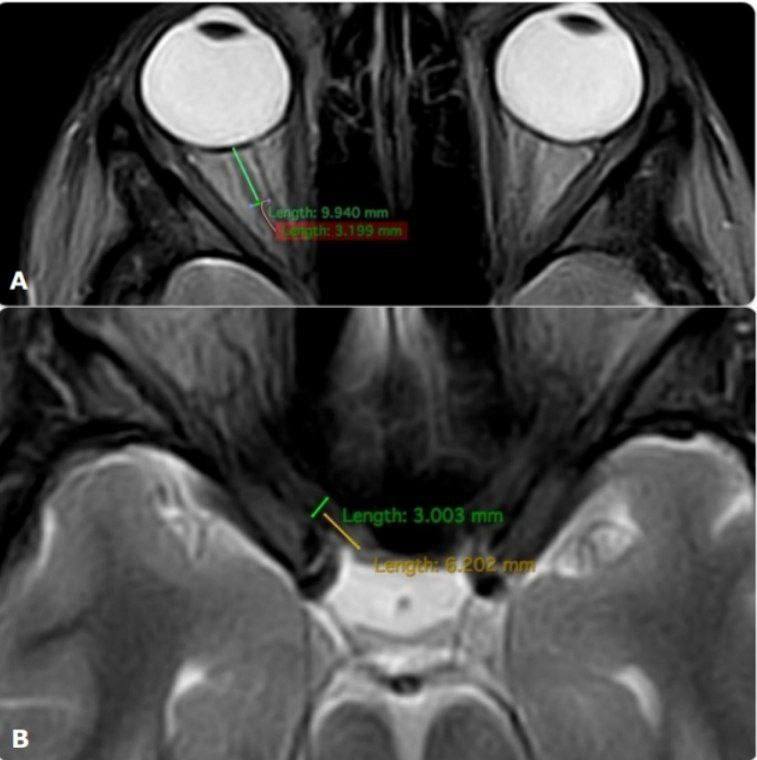

ضایعات بدخیم کبدی و مدیریت آنها: در میان ضایعات بدخیم کبد، کارسینوم هپاتوسلولار (HCC) شایعترین نوع سرطان اولیه کبد است که اغلب در بیماران مبتلا به سیروز یا عفونت مزمن ویروسی کبد دیده میشود. در تصویربرداری CT و